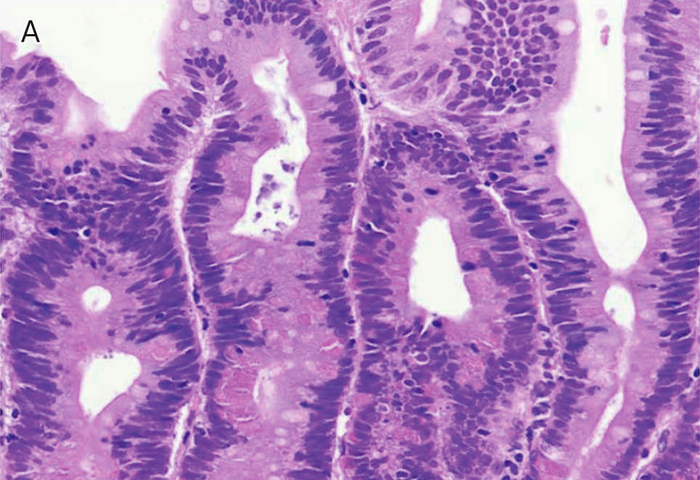

- Spigelman分類は,内視鏡検査で十二指腸腺腫の個数,最大径を評価し,さらに腺腫の組織像(図Ⅱ-9)について,細胞構造と異型度を評価する。現在では若干の修正(修正Spigelman分類)が加えられている92)(図Ⅱ-10)。

| A: | 低異型度腺腫(low-grade adenoma):腫瘍腺管は比較的整然と配列する。小型紡錘形の核が基底側に配列している。 |

| B: | 粘膜内癌:腫瘍腺管は不規則さを増し,核の重層化が目立つとともに核小体もしばしば認められる。Spigelman分類でhigh-grade adenomaとされる病変には,日本の診断基準で非浸潤性の粘膜内癌に相当する病変が含まれる。 |

| C: | 管状腺腫(tubular adenoma):単純な腺管状の増殖を示す。 |

| D: | 管状絨毛腺腫(tubulo-villous adenoma):狭小な間質を伴った絨毛状構造の混在を認める。 |